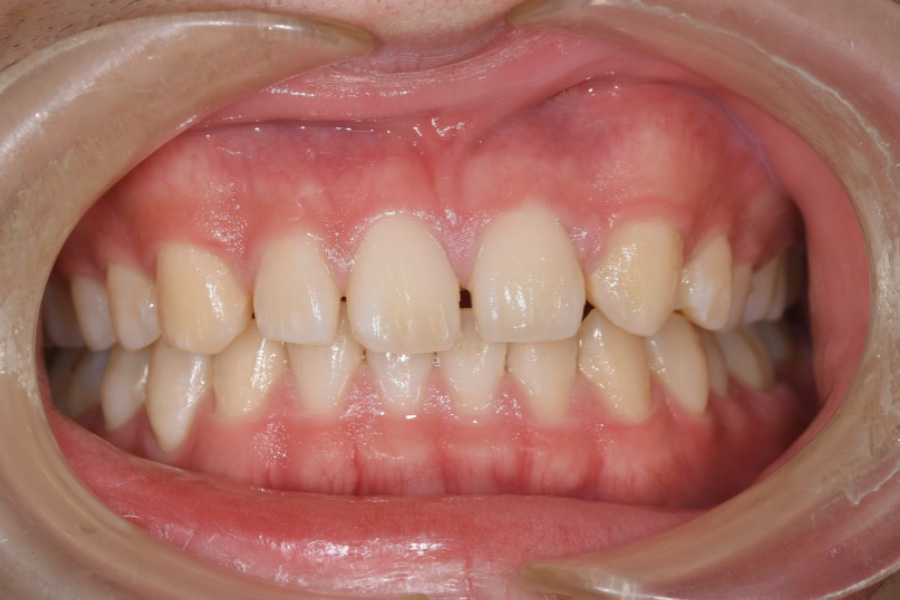

歯並びを治したい

【マウスピース矯正】

- 主訴

- 歯並びを治したい

- 期間

- 2年6か月

- 費用

- マウスピース矯正

935,000円(税込)

- 治療内容

- 目立ちにくいマウスピース矯正(非抜歯矯正)

歯と歯の間に隙間をつくることにより、歯列弓を広げながら治療を行いました。

- 治療に伴うリスク

- ・後戻りする可能性があるのでリテーナーを最低でも矯正期間以上はつけること

・稀にほっぺた、唇、舌などに口内炎や傷ができることがあります